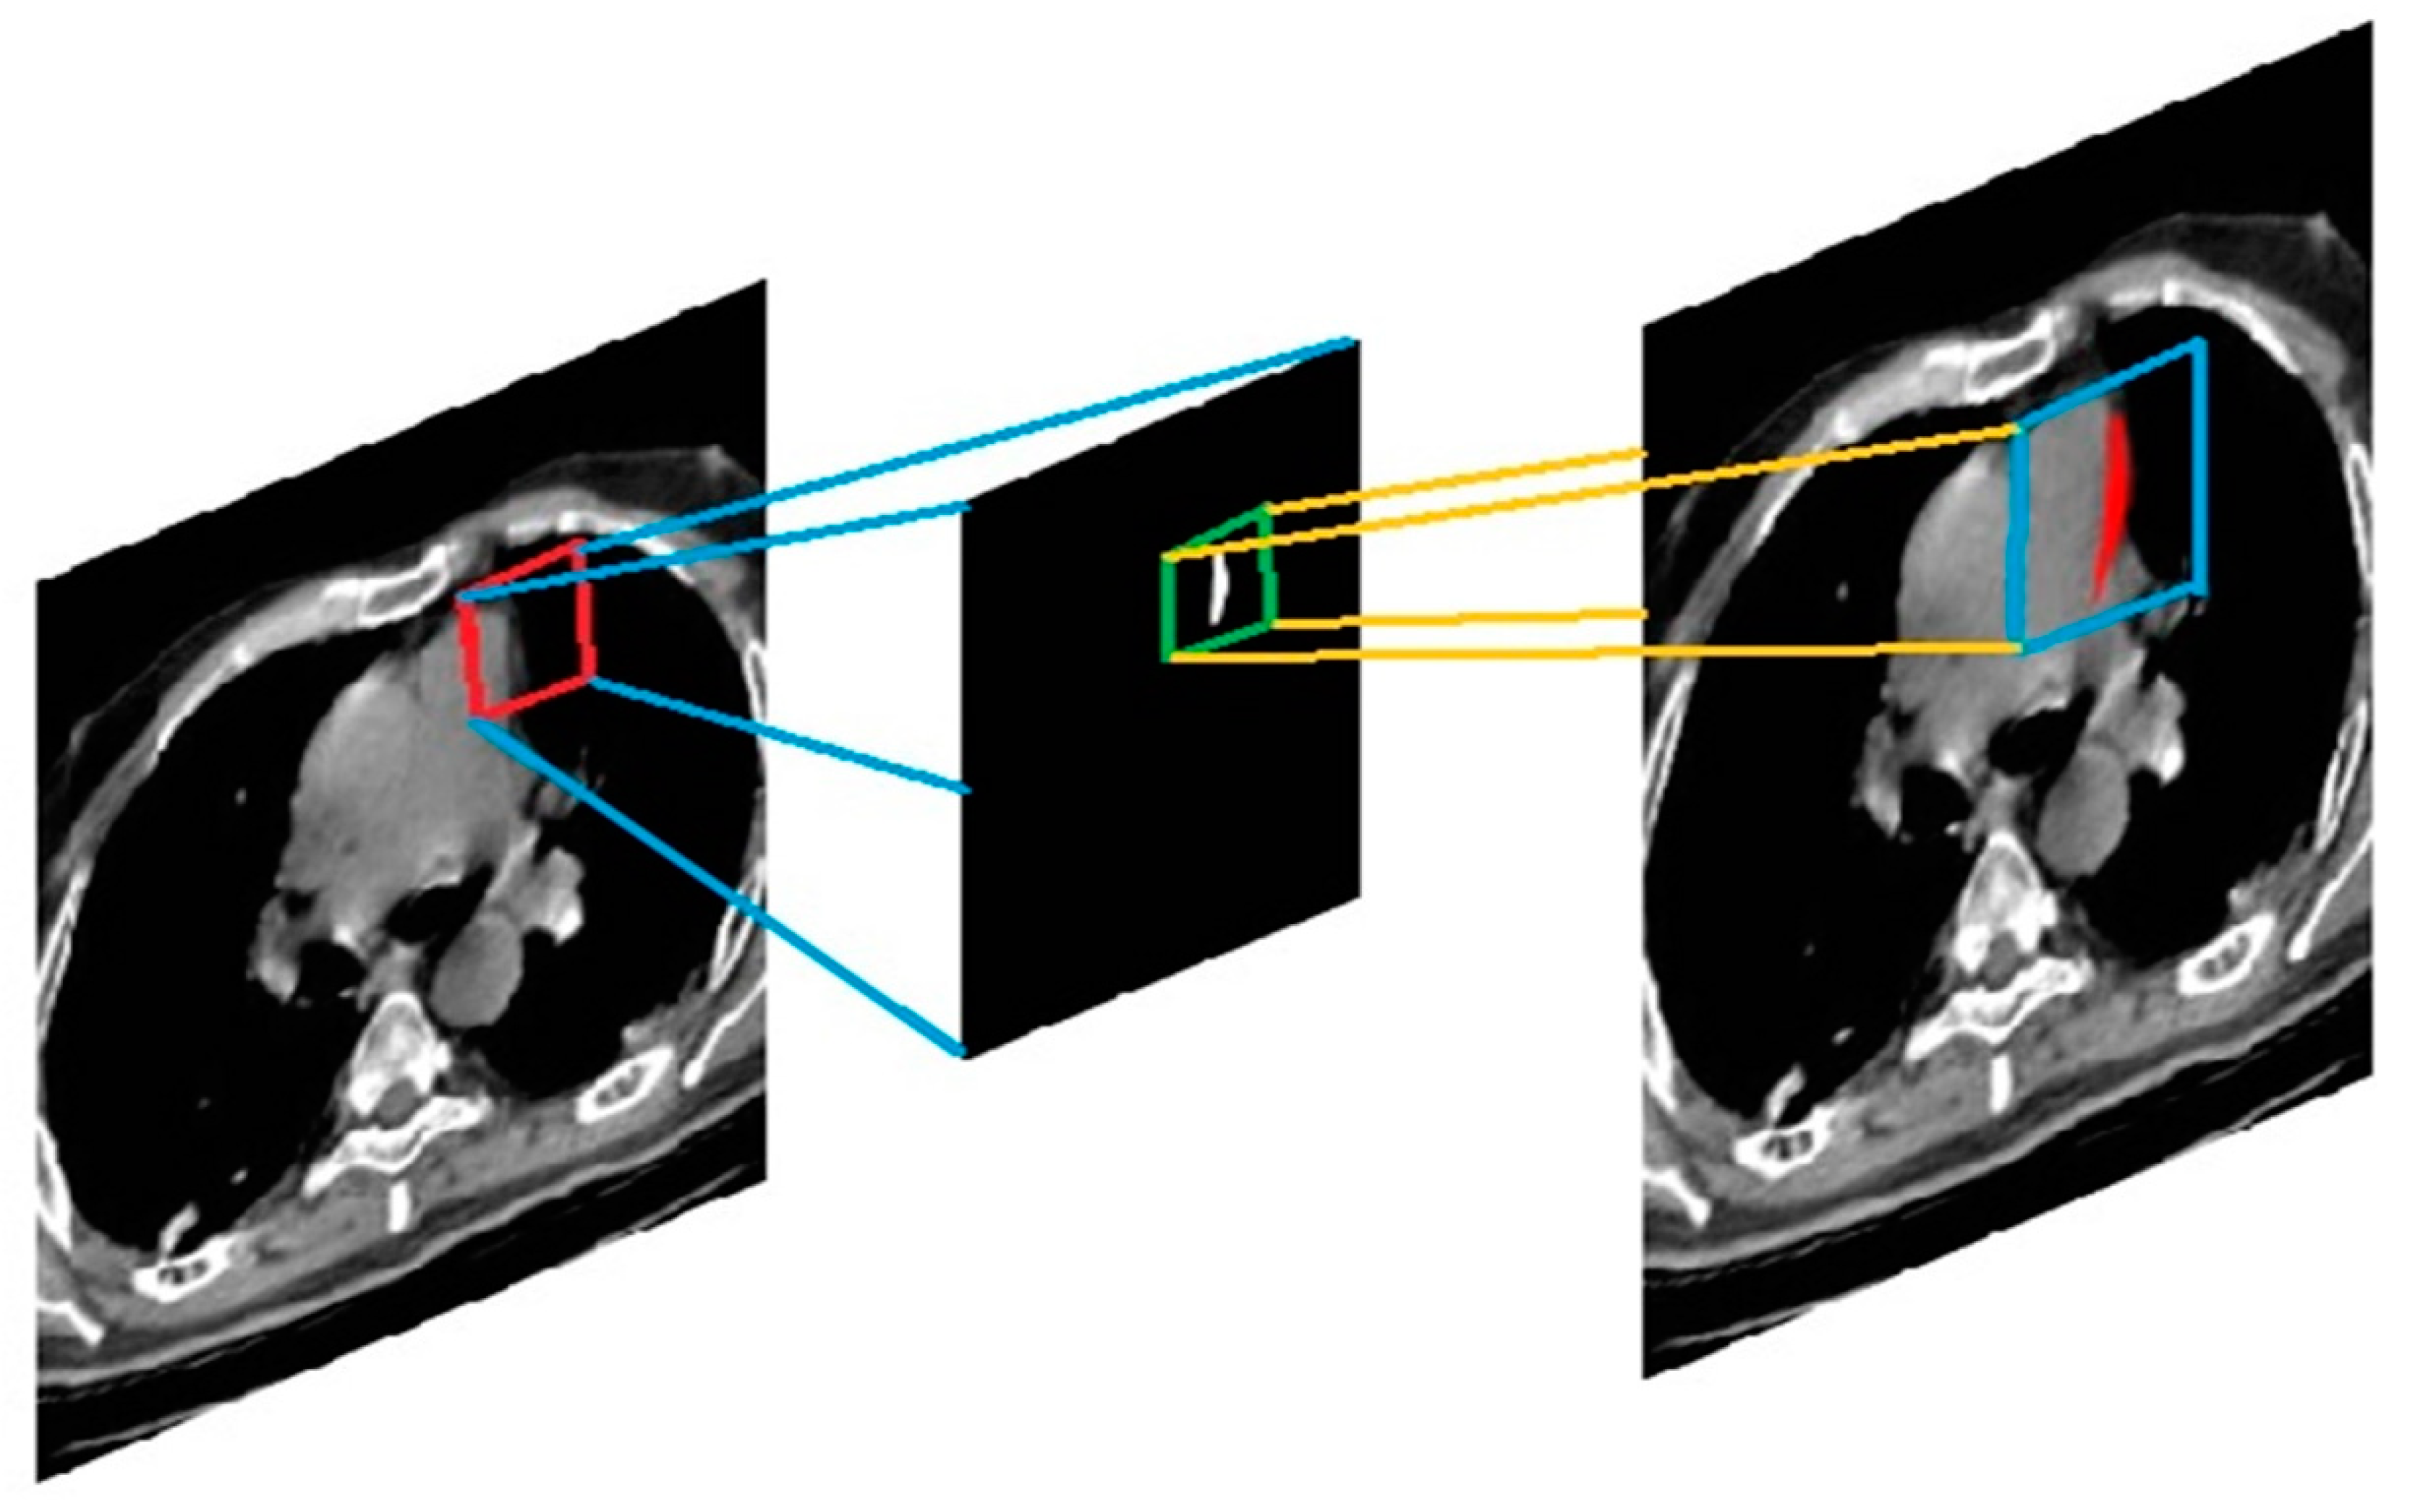

4.2. Segmentation

The segmentation procedure using anticipated filters is depicted in Figure 9. There are three classes in the filtered image. The network’s intermediator output is a three-class tagged picture. We built the output image with this. The enlarged area is represented by the class containing white pixels, the grey matter is represented by the class having grey pixels, and the other region of the image is represented by the class containing black pixels. The two-class labeled image is required in this case to distinguish the pixel density of the enlarged area. The projected label’s class white area is transferred to create a segmented image through every input image with the affected heart enlargement highlighted in red.

Figure 9.

Segmentation process to detect enlarged area.